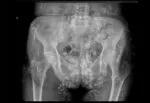

<p>Dystrophic calcinosis occurs in dermatomyositis and is more common in the juvenile form than in this classic (adult) form. This radiograph shows a 78-year-old female with dermatomyositis and extensive calcification of lobular morphology projecting over the majority of the pelvis.</p>

<p>Plaques and exophytic growths significantly restrict this patient’s mobility, making intravenous access and even urination and defecation extremely difficult.</p>